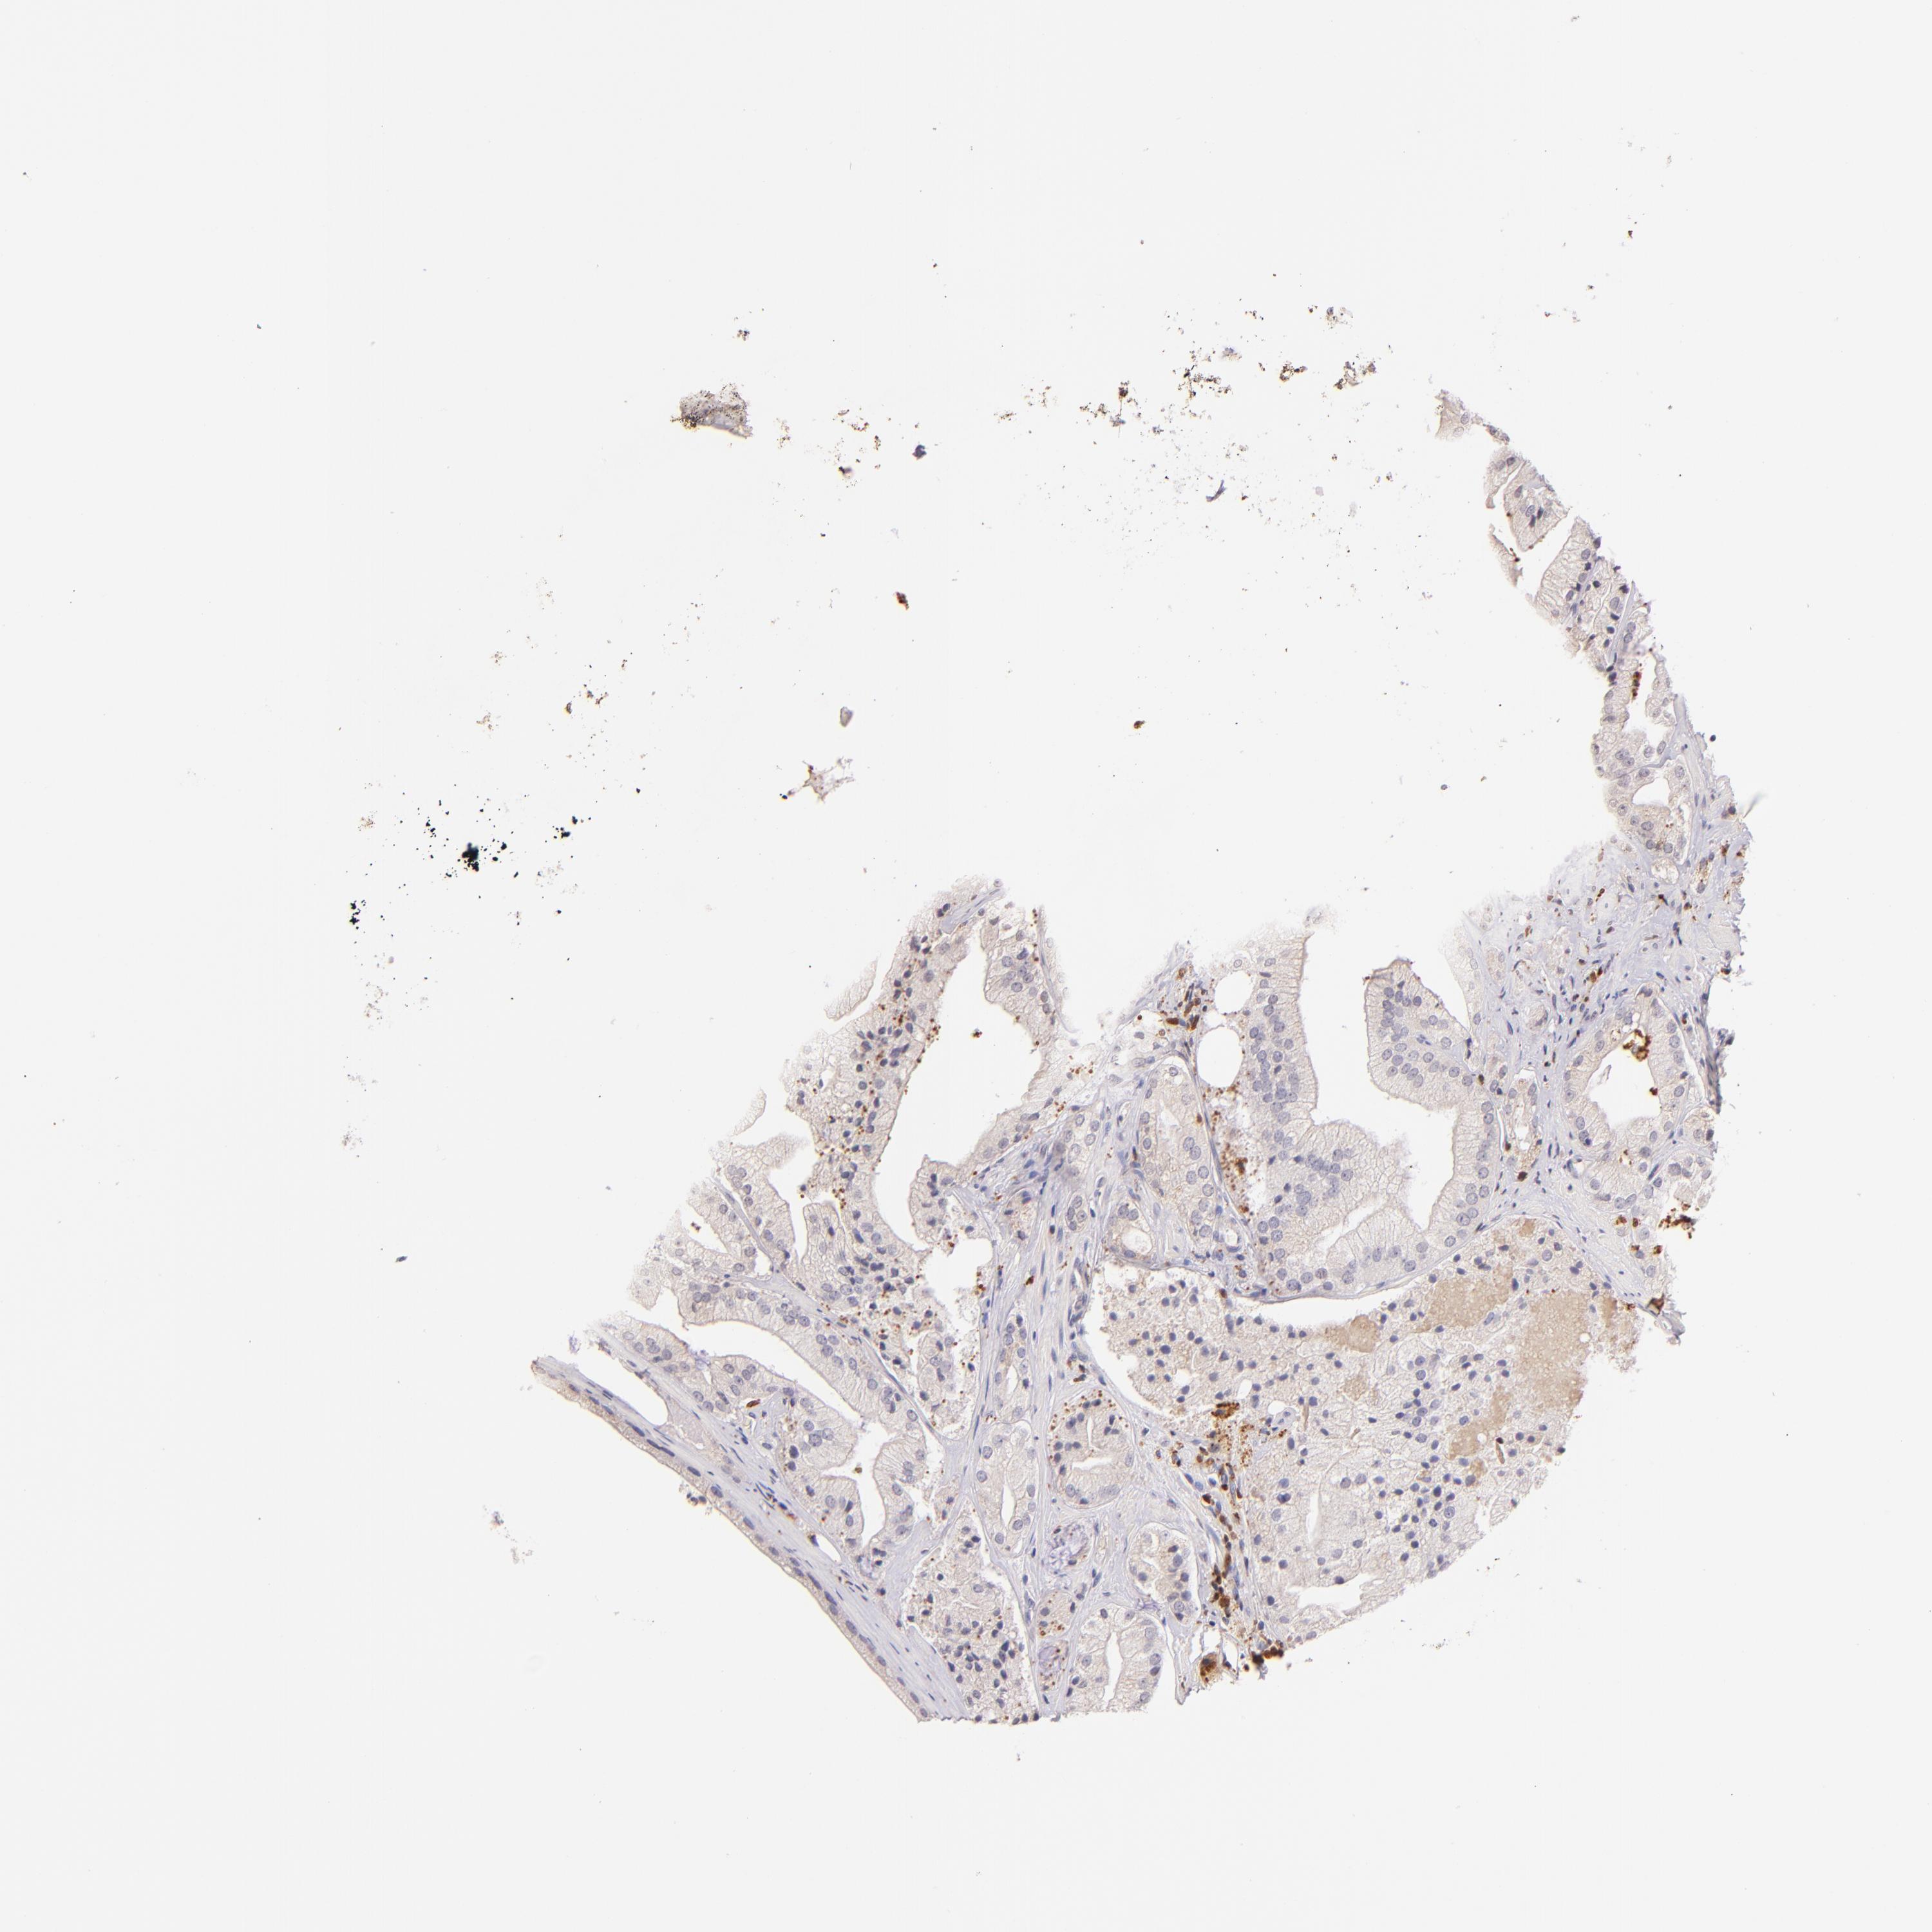

PROSTATE CANCER - Protein expressioni

A mouse-over function shows sample information and annotation data. Click on an image to view it in a full screen mode. Samples can be filtered based on level of antibody staining by selecting one or several of the following categories: high, medium, low and not detected. The assay and annotation is described here.

Note that samples used for immunohistochemistry by the Human Protein Atlas do not correspond to samples in the TCGA dataset.

Antibody stainingi

Antibody staining in the annotated cell types in the current human tissue is reported as not detected, low, medium, or high, based on conventional immunohistochemistry profiling in selected tissues. This score is based on the combination of the staining intensity and fraction of stained cells.

Each image is clickable and will lead to virtual microscopy that enables deeper exploration of all samples and also displays staining intensity scores, fraction scores and subcellular localization as well as patient and tissue information for each sample.

Antibody HPA003134

Antibody CAB002625

Staining

High

Medium

Low

Not detected

Intensity

Strong

Moderate

Weak

Negative

Quantity

>75%

75%-25%

<25%

None

Location

Nuclear

Cytoplasmic/membranous

Cytoplasmic/membranous,nuclear

Adenocarcinoma, Low grade

Adenocarcinoma, Medium grade

Adenocarcinoma, High grade